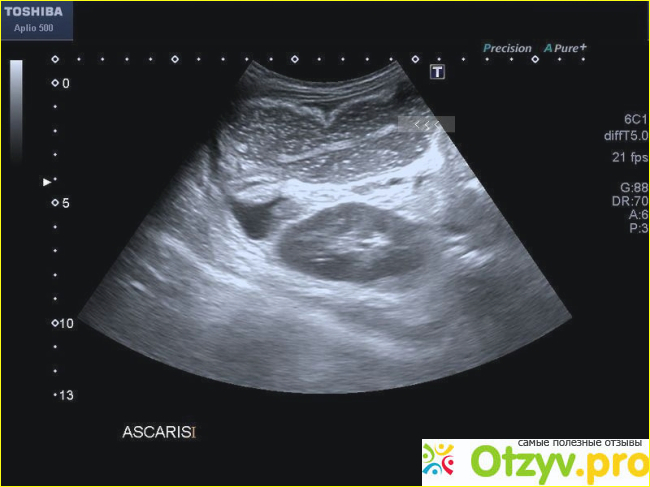

Узи белгород фото1

Узи белгород фото2